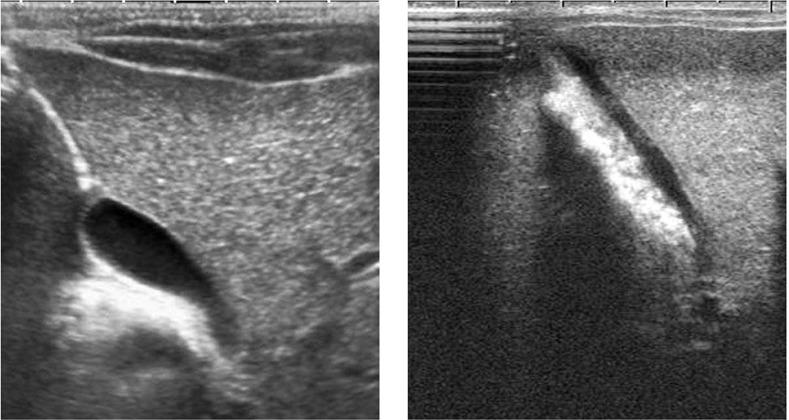

Congenital hypothyroidism is one of the most urgent diseases of the neonate. When diagnosed and treated at an early stage, its most important complication, mental retardation, is preventable. The signs of congenital hypothyroidism are nonspecific in neonates. Only 5% of the cases have characteristic clinical findings. One of the most important and earliest signs is prolonged jaundice during the neonatal period. We report herein a case of congenital hypothyroidism, who presented with icterus accompanied with sludge formation into the gallbladder, which disappeared after treatment with L-thyroxine.

先天性甲状腺功能减退症是新生儿最亟待治疗的疾病之一。若在早期得到诊断和治疗,其最重要的并发症——智力发育迟缓是可预防的。先天性甲状腺功能减退症在新生儿中的体征不具有特异性。仅有5%的病例有典型的临床表现。最重要且最早出现的体征之一是新生儿期黄疸持续时间延长。我们在此报告一例先天性甲状腺功能减退症病例,该患儿表现为黄疸伴胆囊内形成胆泥,经左甲状腺素治疗后消失。